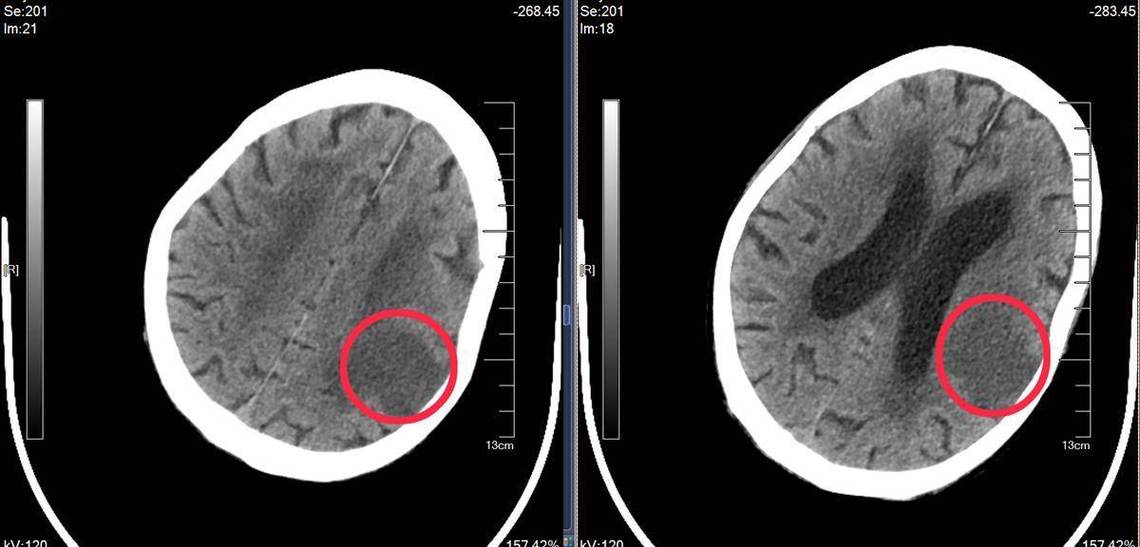

CT的主要作用是“排除”:

- 在急诊,CT的首要任务之一是排除其他可能引起类似症状的疾病,特别是脑出血。

- 脑梗死的CT图像上表现为“白色区域变黑”,而脑出血则表现为“黑色区域变白”(高密度影),这两种病的治疗原则完全相反,所以必须第一时间用CT来区分。